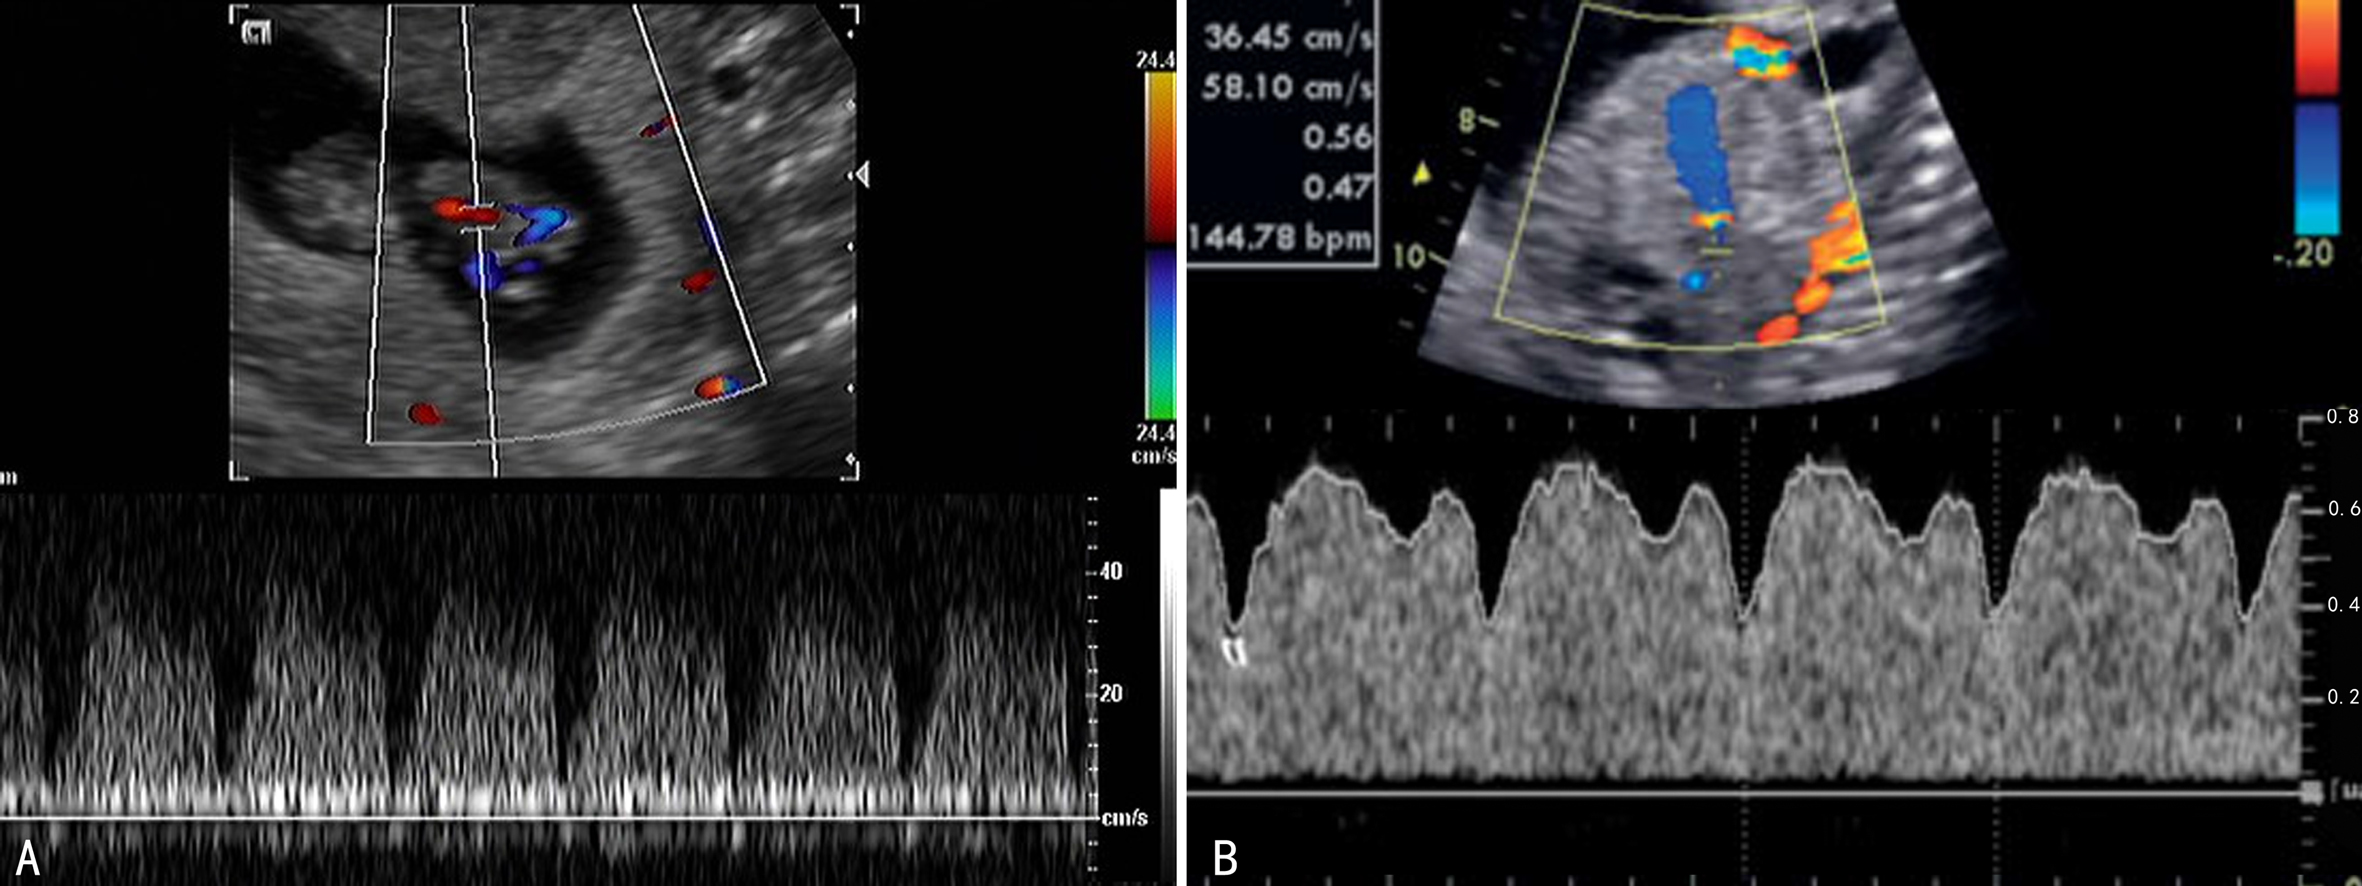

静脉导管(DV)位于门静脉与下腔静脉之间,连接脐静脉腹内段和下腔静脉,细小隐蔽,长4~6mm,直径0.7~1.5mm,在胎儿循环中发挥至关重要的作用。由于管腔狭细,长度较短,需要一定的技巧和经验方可显示。胎动、胎儿呼吸运动及胎位均可影响静脉导管的显示。胎儿安静状态下在胎儿正中矢状切面或胎儿中上腹横斜切面可以显示静脉导管内的血流。正常情况下脐静脉内径较大,静脉导管内径较细,由脐静脉延续的血流至此处流速增加,彩色多普勒血流显像常常显示快速血流镶嵌图形而容易辨认。检查静脉导管时应注意采取连续追踪扫查由脐静脉连续追踪扫查至下腔静脉,适当调节增益、脉冲重复频率并适当缩小取样区域,以准确显示静脉导管及其内部的血流(图4,5)。

图4 11周DV显示 B为A图(俯卧位)的示意图(暗图为未显示结构),C为胎儿仰卧位

静脉导管内血流波形显示为特殊的单向三相频谱,分别为心室收缩期波峰(Vp)、心室舒张期波峰(Vd)和心房收缩期波谷(Va),在整个心动周期中保持前向血流,反映了心动周期中静脉系统和心脏之间的压力阶差变化。血流速度最高的是在心室收缩(心房舒张-快速充盈)期,形成了第一波峰Vp;随着心房的充盈、心房内的压力升高血流速度下降形成了第一个波谷V,与心室收缩末期对应;此后心室舒张、瓣膜开放,心房的血流快速流向心室形成了第二个波峰Vd;在心室舒张末期心房收缩形成了血流速度最低点的第二个波谷Va(图6、图7)。在妊娠11~14周约3%的正常胎儿可显示一反向的a波。

图6 DV多普勒血流参数的测量和计算

图7 DV血流速度曲线(A:11周;B:31周)

衡量指标包括Vp、Vd、Vm、平均时间最大速度(TAMX)、静脉搏动指数(PIV)、静脉峰值速度指数(PVIV)以及前负荷指数[(PLI)=(Vp - Va)/ Vp]和Vp/ Va(S/a)比值等。Huisman等发现静脉导管多普勒血流平均速度为(28.6±6.2)cm/s,是胎儿静脉血管中流速最高的,大于下腔静脉的平均流速(10.9±2.6)cm/s和脐静脉的平均流速(9.7±3.0)cm/s。Tongprasert等和Axt-Fliedner等发现心室收缩速度Vp和心房收缩血流速度Va均随着孕龄的增加相应升高,多普勒指数包括PIV和PVIV随孕周增加而下降。